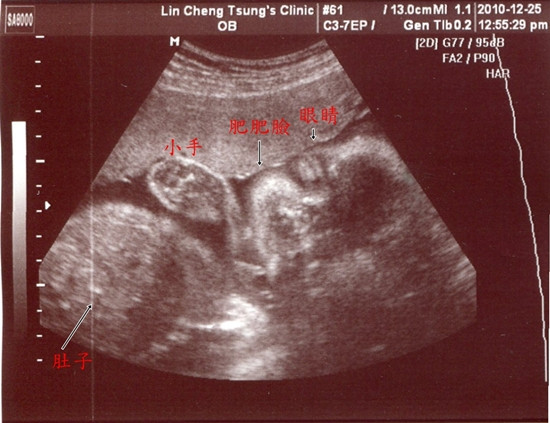

99.12.25這一天我們進行27W的例行產檢

先來張嘴巴張開開的側面照

在林醫師這邊產檢...每次都會照使用高層次超音波來檢查寶寶

因為解析度高...所以用來檢查與判斷器官的成長狀況

看到這張...把小蜜嚇了一跳

才一個月不見...肚子裡的寶貝已經使長肉肉囉!

整個臉肥嘟嘟的...寶寶長大了快一倍...已經1.3KG囉!

我把林小兔養的真好...除了長太大以外...其他的檢查都正常

我最擔心的妊娠糖尿也一次過關...(撒花瓣...轉圈圈...)